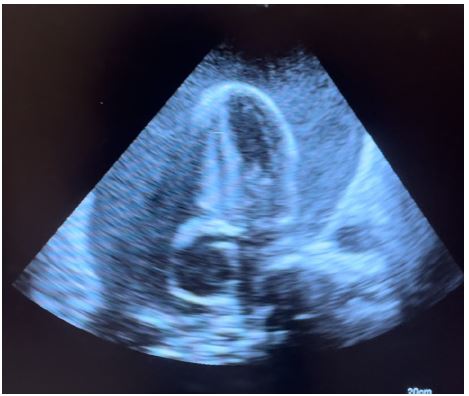

Figure 2: Apical 4 chamber echo view showing massive pericardial effusion with compression of the right side of the heart.

Transthoracic echocardiography is the best diagnostic imaging, useful in diagnosis and management of tuberculous pericardial effusion. Echocardiography can provide an estimate of the size of effusions. Generally, the size of the effusion on echocardiography indicates the volume of pericardial fluid as follows: small (<10 mm), which corresponds to 50-100 mL pericardial fluid; moderate (10-20 mm), corresponding to 100 - 500 mL pericardial fluid and large (>20 mm), corresponding to >500 mL pericardial fluid [19] . The study of Diakité et al. showed 18% of moderate abundance and 81% of high abundance among 49 cases of tuberculous pericarditis [6].